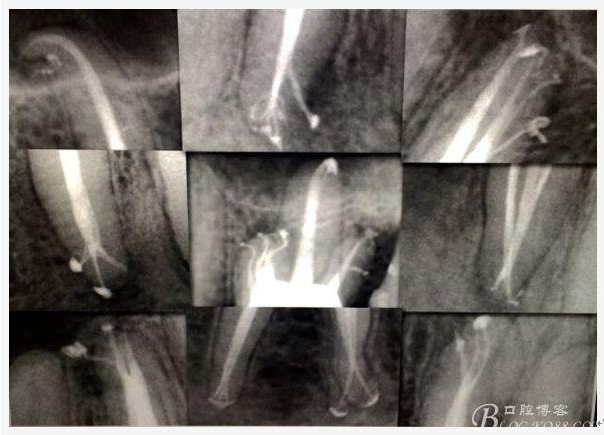

C、牙根的折裂與隱裂 包括橫折,縱折,或者斜折,外傷類的不用討論,主要是某些特殊原因比如牙齒本身結(jié)構(gòu)先天性缺陷再配合后天因素如牙合創(chuàng)傷、咬合平衡發(fā)生改變導(dǎo)致應(yīng)力集中,或者某次瞬間的咬合暴力等一種或者多種因素作用的結(jié)果,具體什么原因這個(gè)要從多方面因素權(quán)衡來(lái)判斷,比如牙齒的松動(dòng)度,詢問(wèn)病史,找不出其它原因時(shí)的重點(diǎn)懷疑,牙齒本事是否處于合應(yīng)力集中的區(qū)域,是否有不良修復(fù)設(shè)計(jì)等等,具體可以通過(guò)臨床“理化檢查(冷熱,叩診等)”再結(jié)合數(shù)值化小牙片,牙髓活力測(cè)定,以及CBCT等來(lái)綜合判斷,重點(diǎn)懷疑牙為上頜的4/5的頰或者腭根,尤其是4或者5的遠(yuǎn)中已是游離缺失或者單端橋等,6的腭根以及下頜的4/5/6都是重點(diǎn)懷疑對(duì)象,而最難診斷的是牙根的隱裂,即使使用CBCT有時(shí)候也沒(méi)辦法確診;

D、牙根的內(nèi)外吸收 這個(gè)目前具體機(jī)制也不是非常明確,只要能想到這個(gè)層面,通過(guò)X片檢查不難發(fā)現(xiàn),尤其到了有臨床癥狀的時(shí)候;

E 、X線影像學(xué)的檢查研判能力: 這點(diǎn)不需要強(qiáng)調(diào)太多,對(duì)于普通的非CBCT的二維影像對(duì)醫(yī)生讀片能力有一定的要求,有個(gè)逐步提高的過(guò)程,非一蹴而就,需要學(xué)會(huì)把二維的X線影像與三維的解剖結(jié)構(gòu)進(jìn)行良好的對(duì)應(yīng)結(jié)合,對(duì)于某些鈣化的髓室底,應(yīng)通過(guò)想象把根管口的分布、根管的走向以及各種變化通過(guò)想象投射到對(duì)應(yīng)的髓室底上;